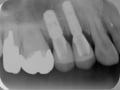

スクリュー固定の場合は、咬む面に小さな穴が空くことになります。しかし、最新の材料を上手く使えばどこに穴が開いていたかわからない位に綺麗に封鎖できます。むしろ綺麗過ぎて、どこが穴がわからなくなることもあるくらいです。なので、接着式に比べ審美性が劣るわけではありません。デメリットは、技工作業が複雑になるので技工物が高価になることとインプラント埋入手術時の位置が良くなければできないことでしょうか。インプラント埋入位置を決めるタイミング

スクリュー固定のねじ穴は、奥歯では咬む面の中央からやや内側付近、前歯では裏側になければなりません。その位置がずれると、セラミックの厚みが薄くなり強度が維持できなくなったり、かみ合わせの力が強くかかる部分にネジ穴がきてしまうことがあります。なので突き詰めると、スクリュー固定で被せ物を作るには正確な位置にインプラントが入っていなければならず、インプラントプランニングの時点で適切で、そのプラン通りの位置に正しく埋入するトップダウントリートメントが必須となるわけです。となると、既存の骨が不足していた場合は骨造成しなければならず、骨のある位置にとにかくインプラントを入れて、さあ被せ物どうしようといったボトムアップトリートメントでは不可能なことが多くなります。原点回帰 スクリュー固定